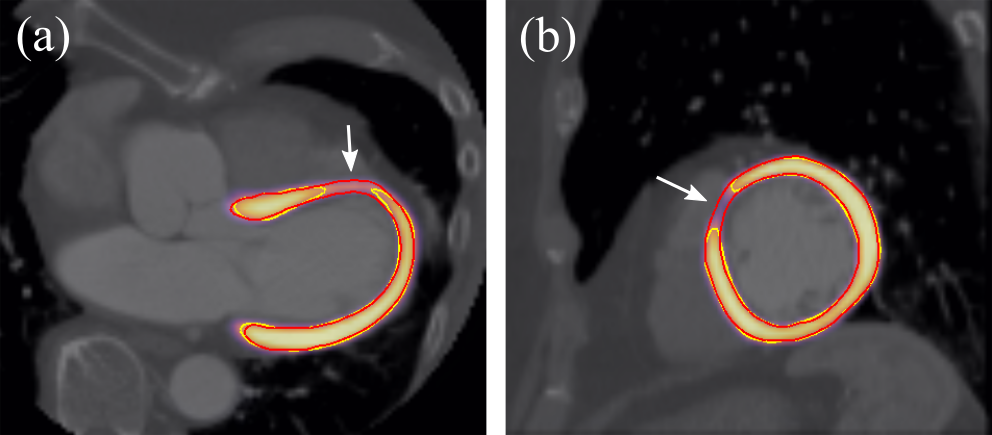

Table 1 shows the results of the U-net and Atlas-ISTN using the high quality 19 case LSA test set, for which labels of all chambers were available. For models trained with no data augmentation, we observe slight improvements of the ITN over the U-net for LVM, LV and RV DSC (, and , respectively), but not for other structures. The 1-pass performance of Atlas-ISTN falls short of the ITN across all metrics for the aforementioned reasons. Refinement produces the best results across almost all metrics, and although DSC improves by a moderate over the ITN, performance on ASD and HD metrics improves significantly. U-net1cc also improves over the U-net in terms of HD and to a lesser extent ASD, but is almost always out-performed by refinement. Fig. 11 shows examples where U-net1cc is unable to correct certain false positive and false negative predictions, while refinement of Atlas-ISTN does.

We observe that U-net1cc improves over the U-net performance both with and without augmentation, and also out-performs the ITN model trained with spatial augmentations. Refinement still produces the best results across both augmentation settings, despite a lower ITN performance compared to the U-net and U-net1cc with augmentation. Additionally, the result of refinement guarantees topology and encourages smoothness of the target structures while U-net1cc does not (see examples in Fig. 11). Statistically significant improvement across all metrics is achieved with refinement compared to all other models.

Results on the 1000 case test for these LVM-only models trained with an additional 2000 cases are presented in Table 5. Interestingly, the ITN out-performs the U-net across all metrics, with a DSC increase. The ITN also performs better than the 1-pass and refinement for DSC and ASD. Refinement improves over the ITN, 1-pass and U-net in terms of HD, and performs similarly to the U-net for DSC and ASD. It should be noted that although the ITN out-performs refinement on DSC and ASD, differences between segmentations with DSC become practically insignificant. Inter-observer DSC for LVM segmentation from cardiac short-axis cine MRI for example is 0.88 [6], which one might expect to be slightly higher for segmentation from 3D CCTA images. Also, despite being trained using a significantly larger dataset, the ITN is still prone to predictions with holes, particularly for cases with thin LVM walls, which can be rectified by refinement (Fig. 13).